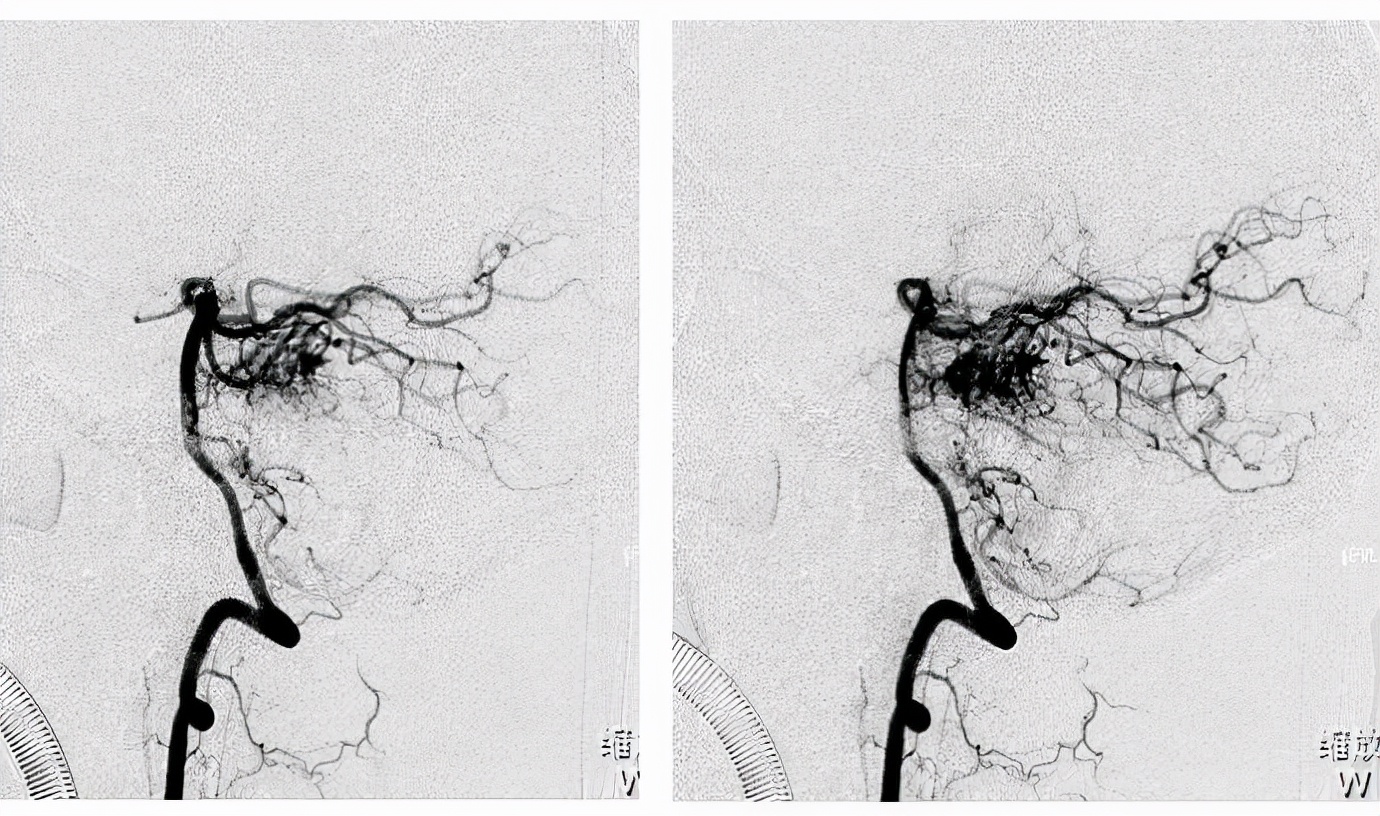

需要提醒的是,动静脉畸形患者因其血液淤积,可致局部疼痛、溃疡或反复出血,严重者可形成血栓或引起肢体坏死而截肢,甚至累及心脏,导致心衰而危及生命。所以,凡新生儿身上有不明原因的肿块,须及时到医院检查。医生可通过彩色多普勒超声、磁共振成像、非创伤性血管成像术及数字减影血管造影等检查,排除血管瘤、静脉畸形、淋巴管畸形后予以确诊,并给予针对性的治疗。